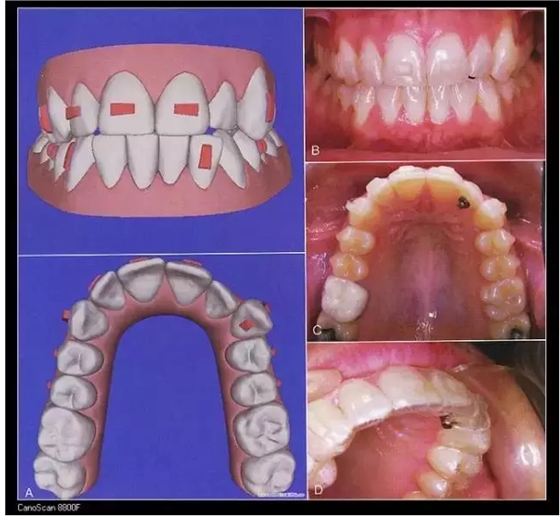

Invisalign隱形矯治器的原理是先在計(jì)算機(jī)里對(duì)醫(yī)生的印模進(jìn)行三維建模,按照正畸醫(yī)生的指導(dǎo)來(lái)設(shè)計(jì)挪動(dòng)牙齒,得到醫(yī)生的確認(rèn)后投入加工。每付矯治器少量移動(dòng)牙齒,兩周更換一副矯治器,在1-2年后完成牙齒的矯治。因?yàn)椴馁|(zhì)沒(méi)有金屬,受到很多白領(lǐng)的追捧,不過(guò)目前還不能夠治療所有的復(fù)雜病例。對(duì)付輕中度擁擠,輕度開合,牙縫散開等是不錯(cuò)的選擇。